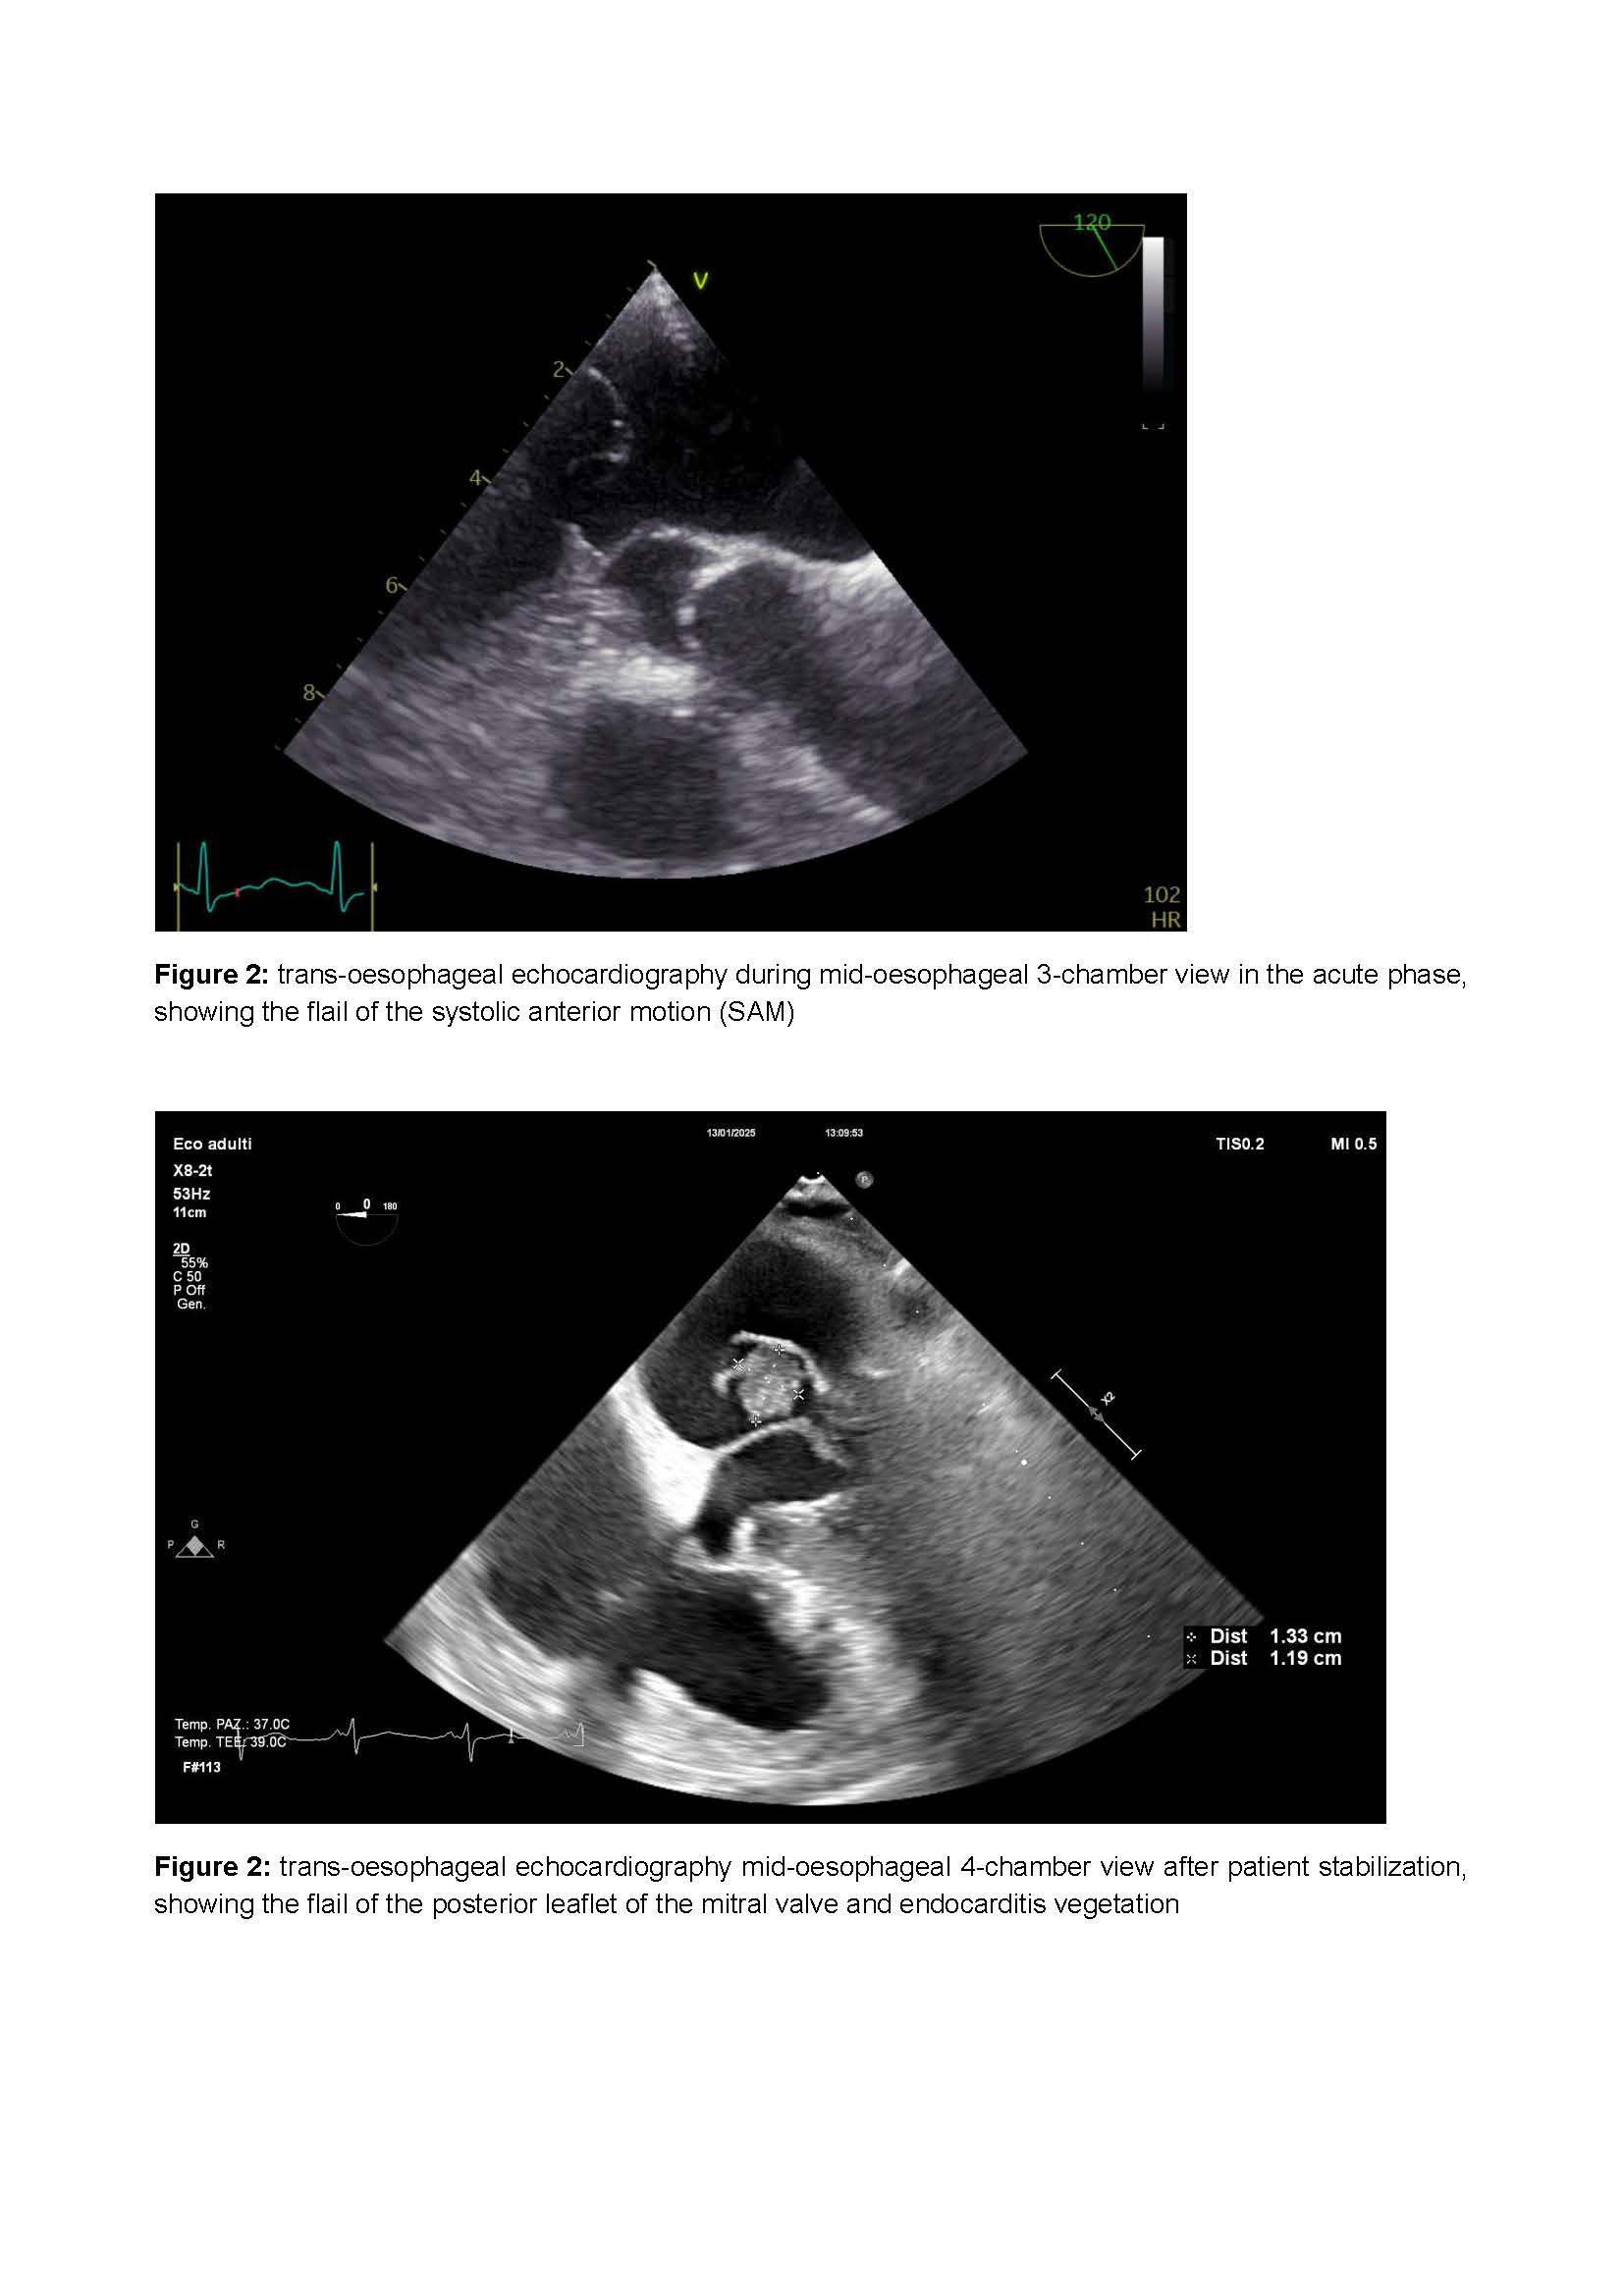

Introduction: dynamic left ventricular outflow tract obstruction (LVOTO) due to systolic anterior motion (SAM) causes various grades of mitral regurgitation (MR), potentially hiding structural valve disease. Case report: we present a case of an 82-year-old patient admitted to cardiac intensive care unit (CICU) due to cardiogenic shock and acute respiratory failure caused by severe MR, hiding mitral valve vegetation. MR resulted from flail and perforation of posterior mitral leaflet (PML), combined with dynamic LVOTO due SAM of anterior mitral leaflet (AML). Discussion: careful avoidance of same therapy and devices indicated in MR, like sodium nitroprusside and intra-aortic balloon pump (IABP), is essential to avoid worsening of LVOTO and thus hemodynamic stability. Instead, the use of drugs to obtain pressure equalization and negative chronotropism, such as norepinephrine and selective beta-1 receptor blockers, significantly reduce LVOTO and thus the MR, achieving hemodynamic stability and showing valve anatomy. Conclusion : our case-report underscores the importance of a multidisciplinary approach in the management of complex valvular dysfunction, particularly when dynamic LVOTO complicates the clinical presentation. Careful hemodynamic modulation can not only improve patient stability but also facilitate accurate diagnostic assessment, ensuring timely and appropriate therapeutic interventions. Keywords: dynamic left ventricular outflow tract obstruction, systolic anterior motion (SAM), mitral regurgitation, endocarditis, shock, valvular heart disease. Contribution type : case report